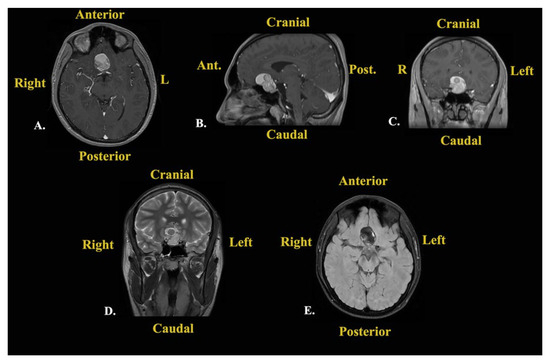

The patient was reevaluated by the endocrinological department at 3 months. Still, his corticotroph deficiency had persisted, and the patient was advised to continue his substitutive corticosteroid treatment at the same doses and in the same manner. At the 3-month follow-up, contrast-enhanced brain MRI was performed, which showed no recurrences or abnormalities (Figure 8).

Figure 8. Contrast-enhanced brain MRI (T1-weighted sequences) performed at the 3-month follow-up.